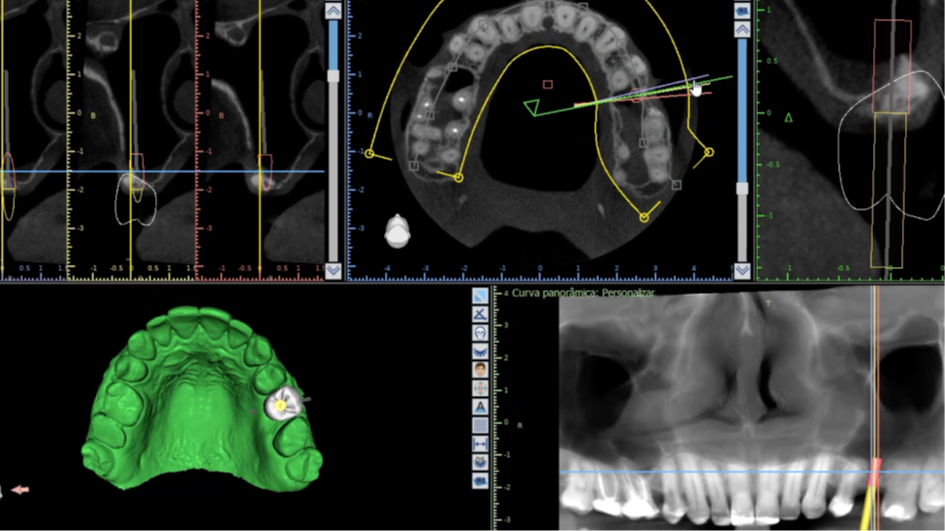

Nas últimas décadas, as reabilitações orais têm sido revolucionadas pela utilização de implantes dentários ósseointegráveis, apresentando uma taxa de sucesso superior a 90%.1 Porém, a maxila posterior edêntula pode dificultar a reabilitação implantossuportada, podendo impor severas limitações anatômicas, causadas pela baixa densidade e possível atrofia do osso alveolar, bem como o processo de pneumatização do seio maxilar.2,3

O processo de pneumatização ocorre devido a atividade osteoclástica da membrana schneideriana em resposta a pressão positiva do ar dentro da cavidade paranasal e a qualidade tipo IV mais macia do tecido ósseo maxilar.4

O presente trabalho tem como objetivo fazer um relato de caso clínico de reintervenção em enxerto ósseo para levantamento de seio maxilar pela técnica da janela lateral com instalação simultânea de implante Maestro Superiore.